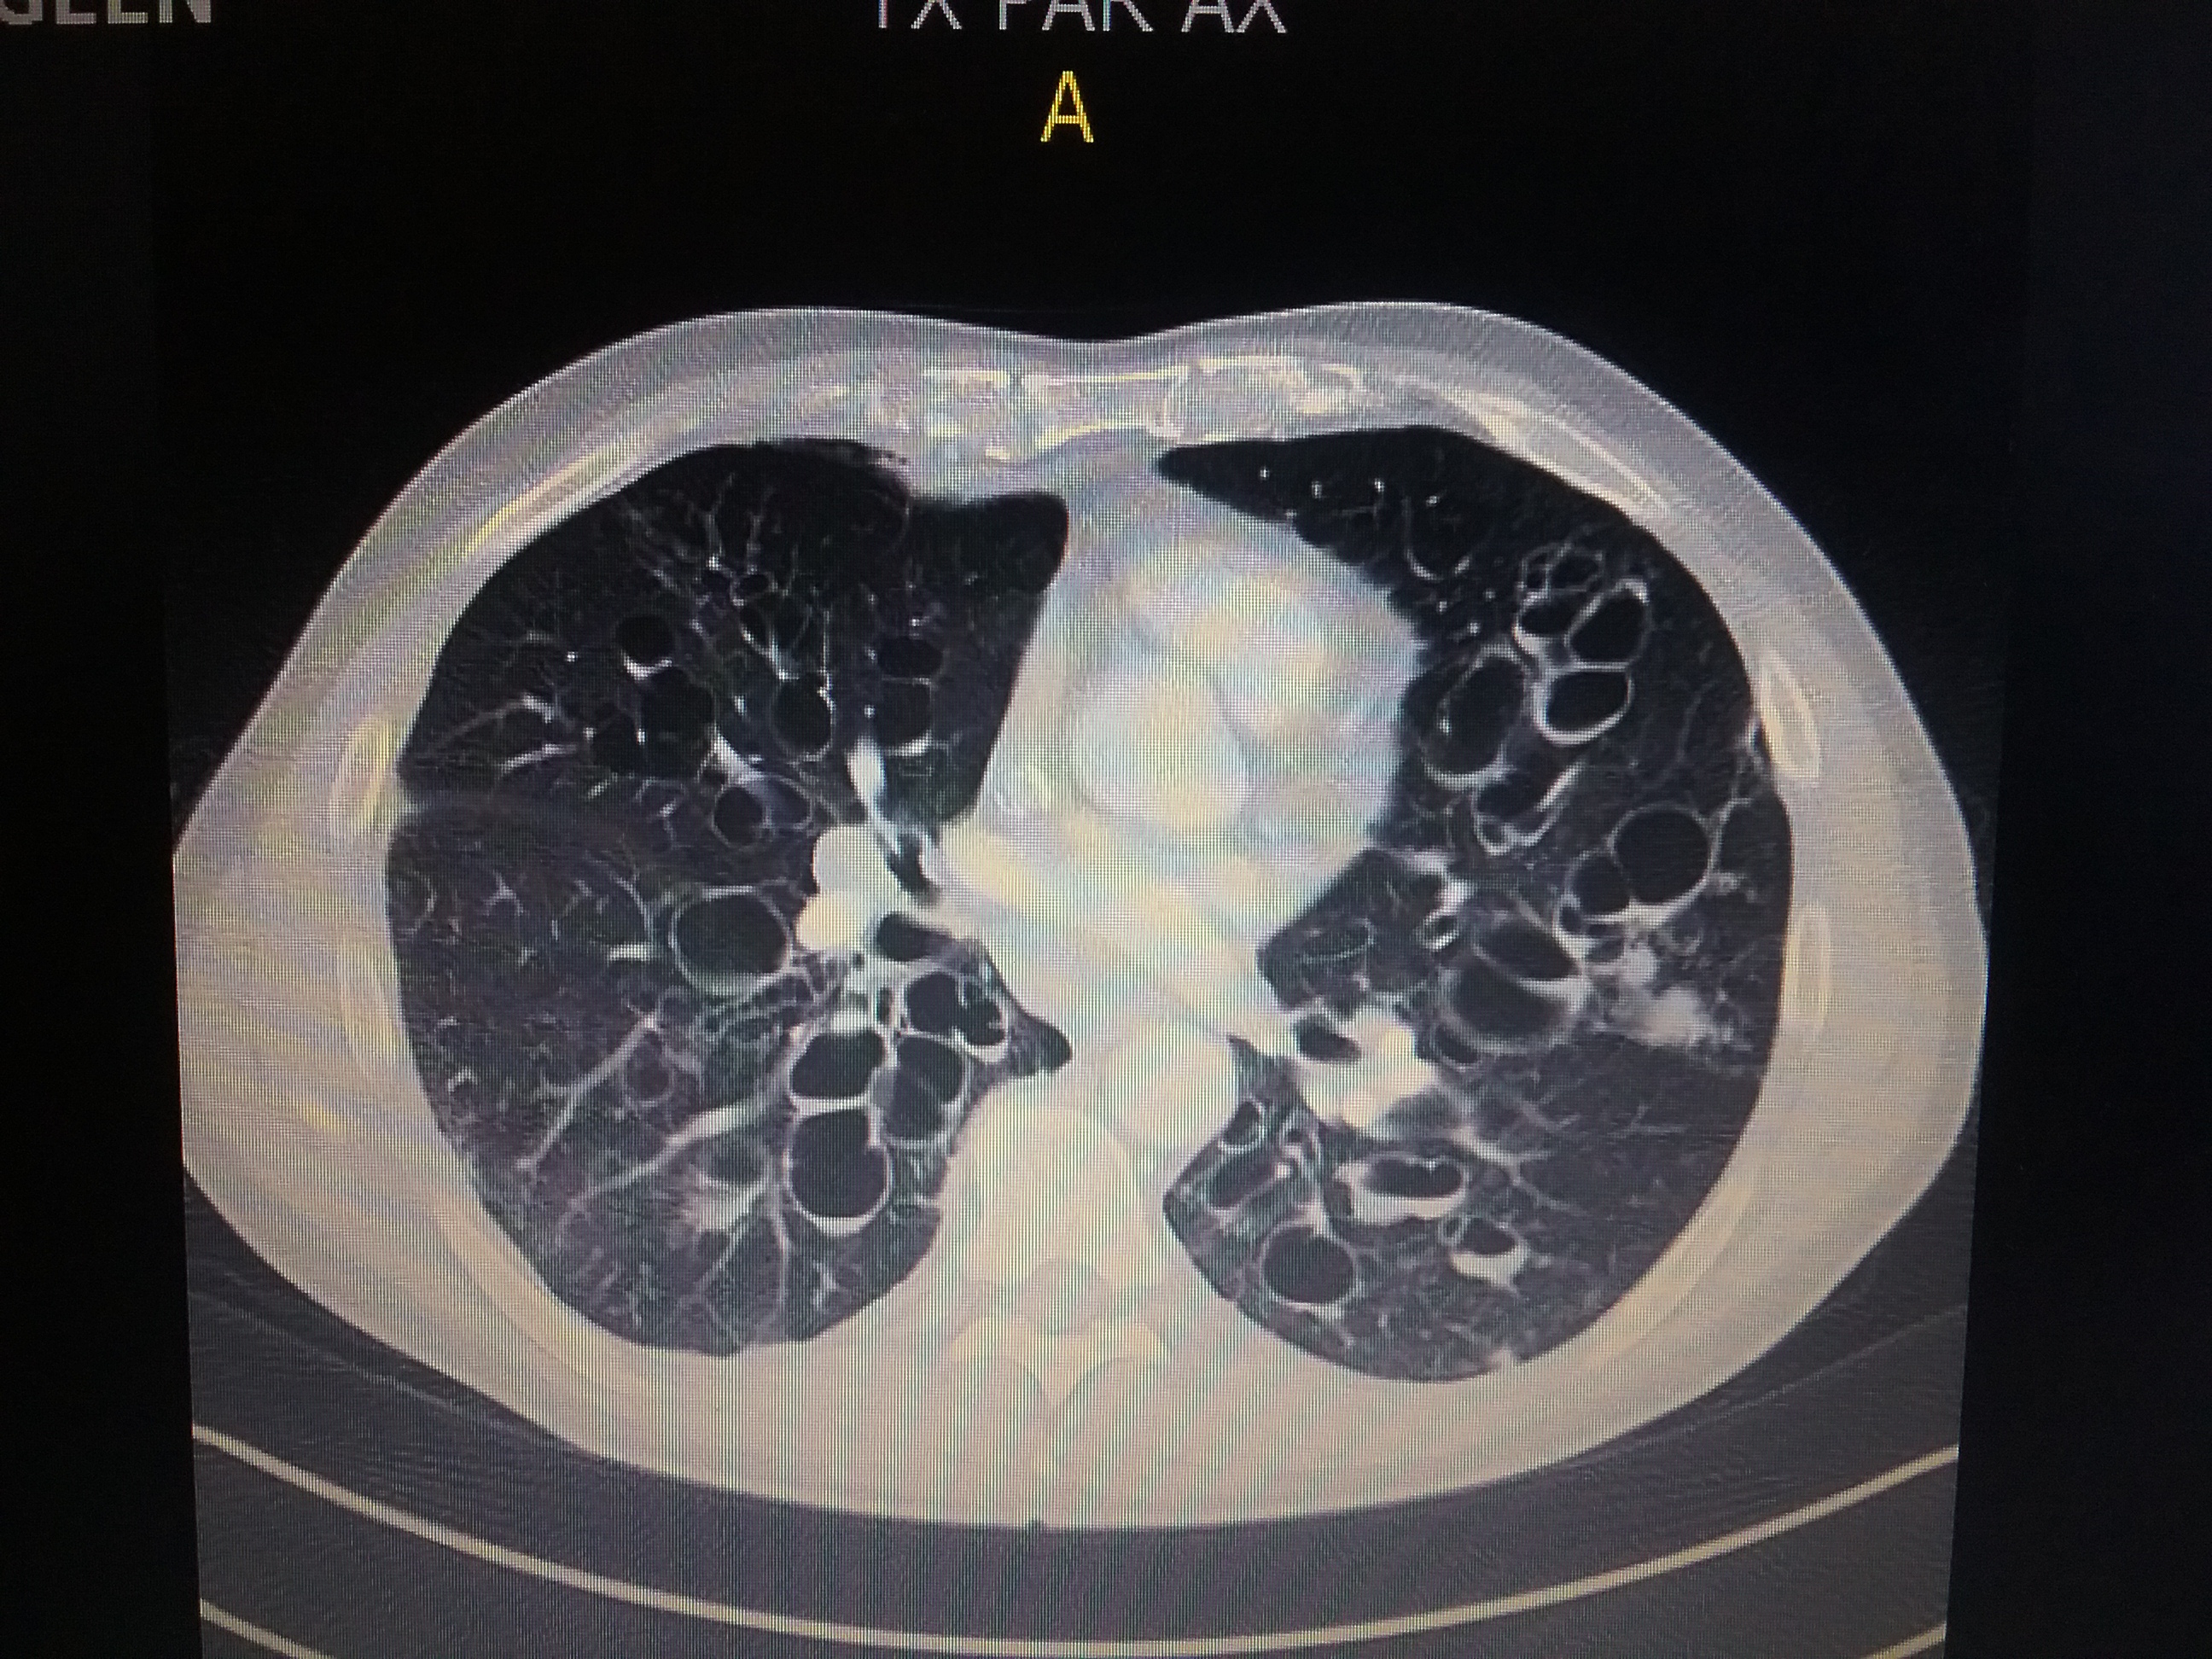

Ik heb altijd al graag met plantjes zitten prutsen. Toen ik ging wonen waar ik nu woon, was ik echt blij dat ik wat plaats had voor een kleine moestuin. Een ‘lochtingske’ zoals dat hier in de volksmond heet. Jarenlang heb ik dat met plezier gedaan. En toen kreeg ik een soort zeldzame en dodelijke longziekte. De laatste jaren was ik daardoor niet meer in staat om veel uit te spoken. Ik werd afhankelijk van zware pijnmedicatie, hing op het einde 24/7 aan een zuurstofslang, en werd erg beperkt in m’n fysieke mogelijkheden. Meer dan enkele tomaatjes, pepers, komkommers en rode bieten kon ik, ondanks die extra zuurstof, fysiek niet meer aan. Bovendien moest ik elke tien weken voor twee weken naar het hospitaal. Mensen in mijn omgeving prezen mij evenwel voor zoveel levenslust en optimisme, maar misschien was het niet meer dan een koppige moed der wanhoop, een tegen beter weten in vastklampen aan grote en kleine dingen die een mens alsnog gelukkig maken. Al is het mogelijks precies dát waar het leven om draait, of zou moeten draaien. Weet ik eigenlijk veel.

Drie maanden geleden onderging ik dan de levensreddende longtransplantatie. Ik ben nu volop aan het revalideren daarvan, zit alweer boordevol energie, en ik kan niet wachten om terug aan de slag te gaan in mijn klein lochtingske. Volgens de dokters moet ik wel voorzichtig zijn en bepaalde voorzorgen nemen tegen allerlei besmettingsgevaar. Mijn lichaam zit immers vol medicijnen die afstoting van de donorlongen moeten voorkomen, maar die eveneens m’n natuurlijke weerstand tegen bacteriën en schimmels sterk onderdrukken. En aarde en compost zitten nu eenmaal tjokvol bacteriën en schimmels. Maar goed, ik ga terug moestuinieren. En ik ga daar dus over schrijven. Het wordt vast een fijn lochtingseizoen.